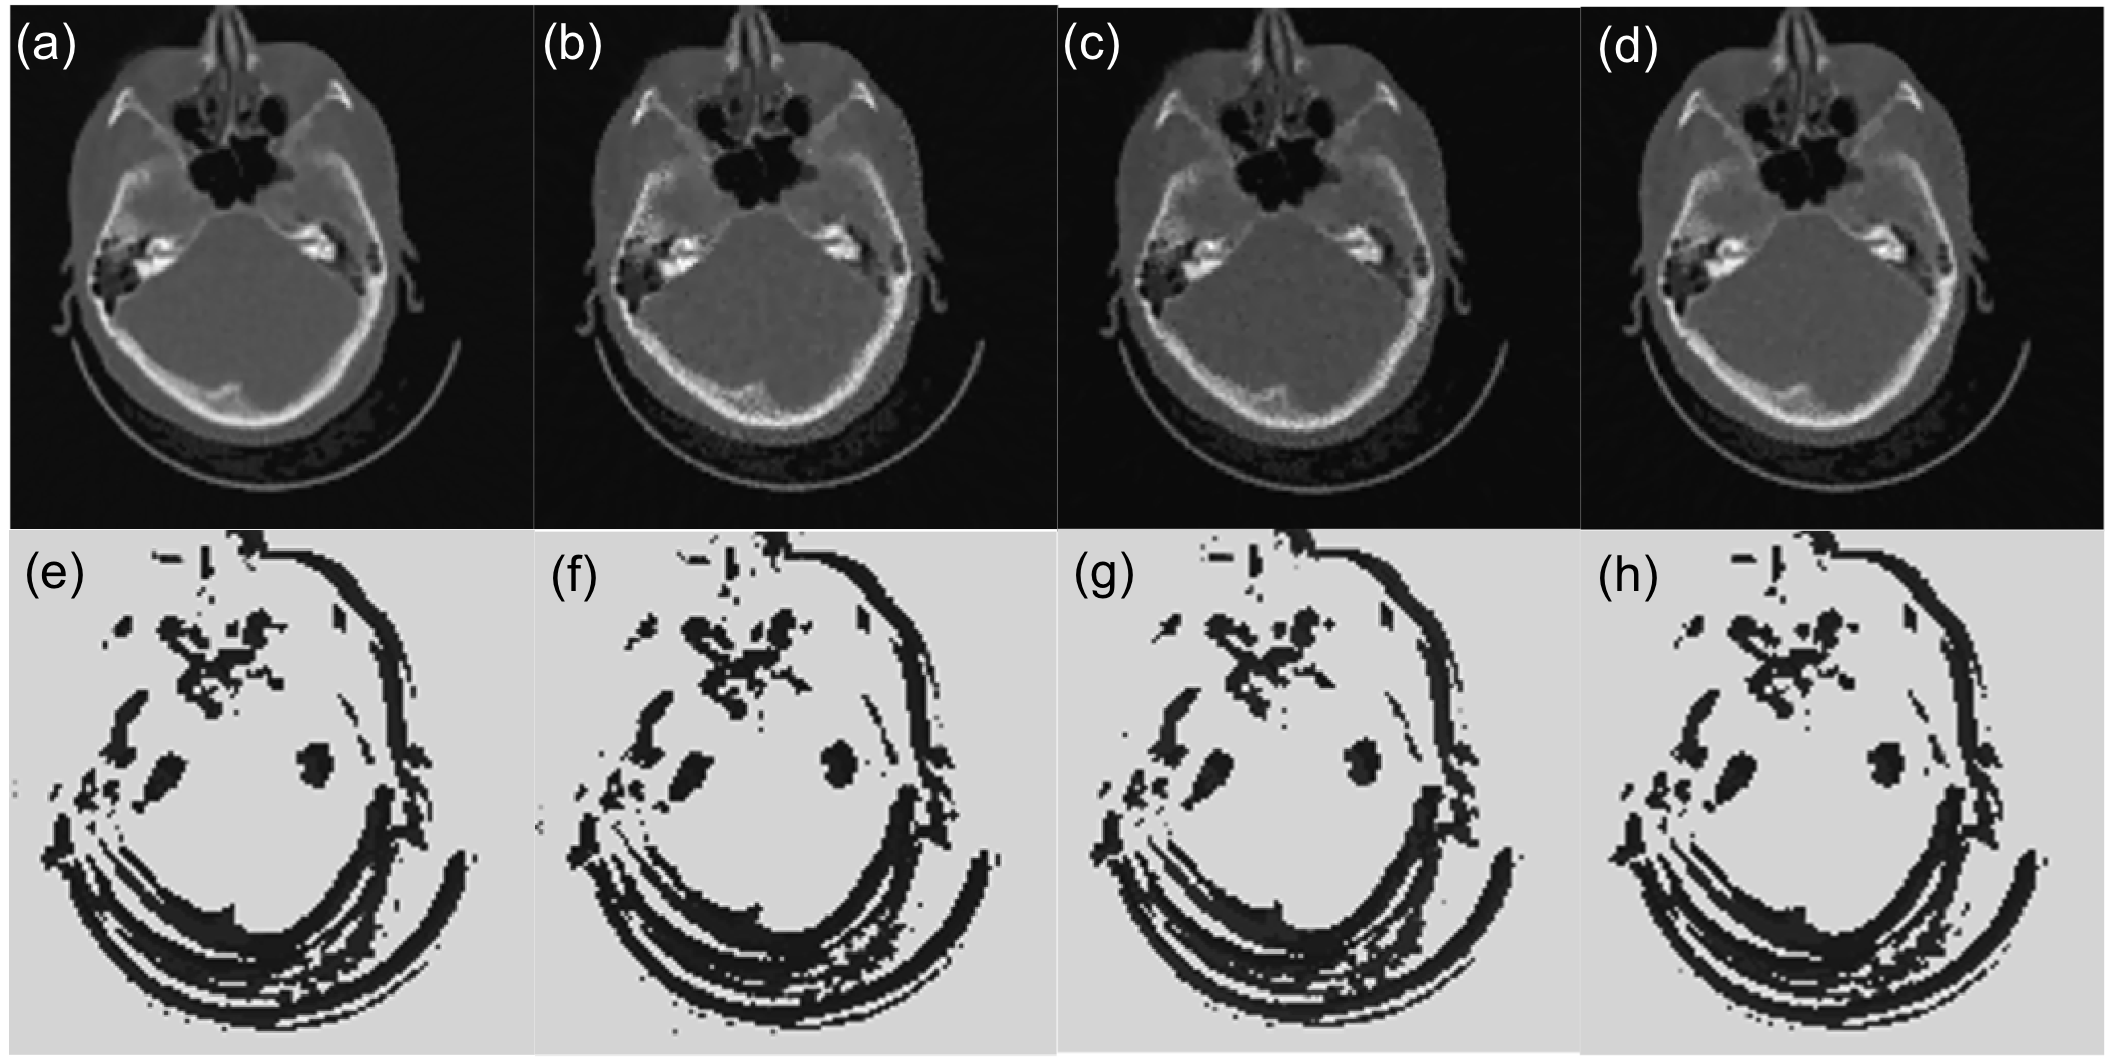

III-B3 Application to other cases

The PTPN determines the way of parameter tuning based on observed image patch. It is expected that the trained PTPN is also applicable to image reconstruction under settings that are different from that in training. To demonstrate this fact, we also applied PTPN to image reconstruction in cases with different number of projections, noise levels, and projection geometry. Fig. 8(a) and (b) are the same case as in Fig. 7 but with and noise in the projection data, different from the noise level of in training. Fig. 8(c) is the case with only projections. In Fig. 8(d) we change the isocenter-to-detector distance to cm. In all the cases, PTPN is able to adjust parameters to yield images with satisfactory quality. The resulting parameter maps in Fig. 8(e)-(h) are all similar to the ground truth shown in Fig. 7(f).